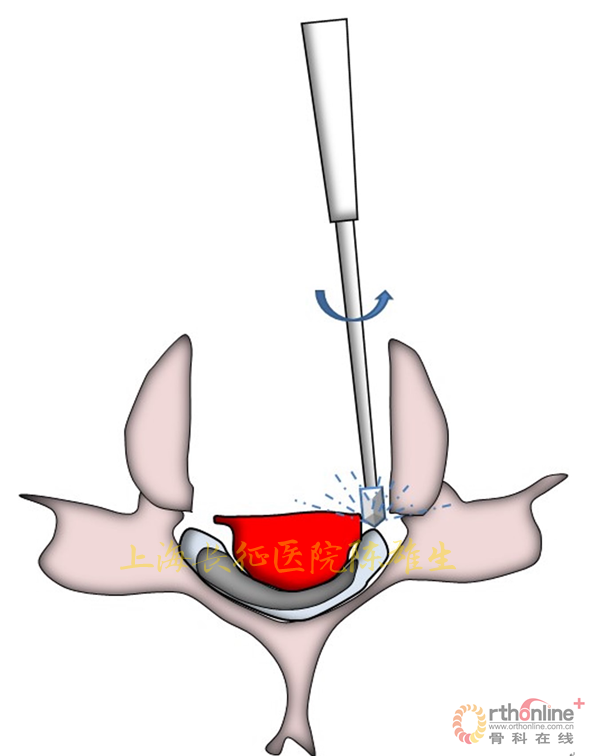

3.2.2骨化物漂浮,初步缓解脊髓压迫

磨钻磨透骨化物周围骨结构;剥离子游离骨化物边界,使之漂浮,初步缓解脊髓压迫(图13)。

图13